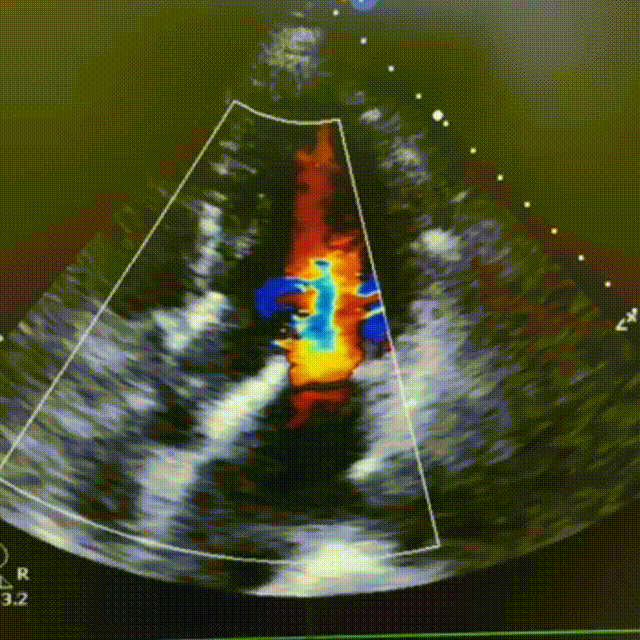

超声影像

TTE下主动脉瓣短轴和五腔心角度下,血流动力学结果优异,反流即刻消失。